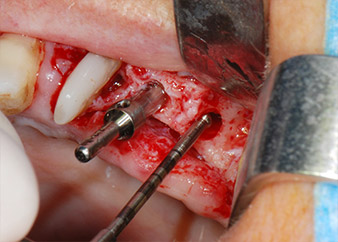

One month later, on the day of surgery, pain and inflammation at tooth 24 were minimal, but mobility of Miller class 2 was still present. After opening the flaps and cleaning the periapical and peri radicular infected tissue, the extent of the bone defect became obvious (Figs. 2 and 3).

At the buccal root, all vestibular and distal bone was missing. Attachment was essentially restricted to the palatal root, underlining the preliminary poor prognosis. Tooth 27 also showed a reduced horizontal attachment and a minimal apical rarefaction (cf. Fig. 1) without clinical symptoms.

However, we maintained our initial plan to retain both teeth as temporary bridge abutments during the six-months osseointegration period of the implants. At reentry, the situation would have to be reassessed. First, in an attempt to manage the endo-perio problem, the remaining root surface was carefully debrided with piezoelectric equipment (Piezomed, W&H, used with the spatula-shaped insert S1, originally designed for erosion of the lateral sinus wall) (Fig. 4).